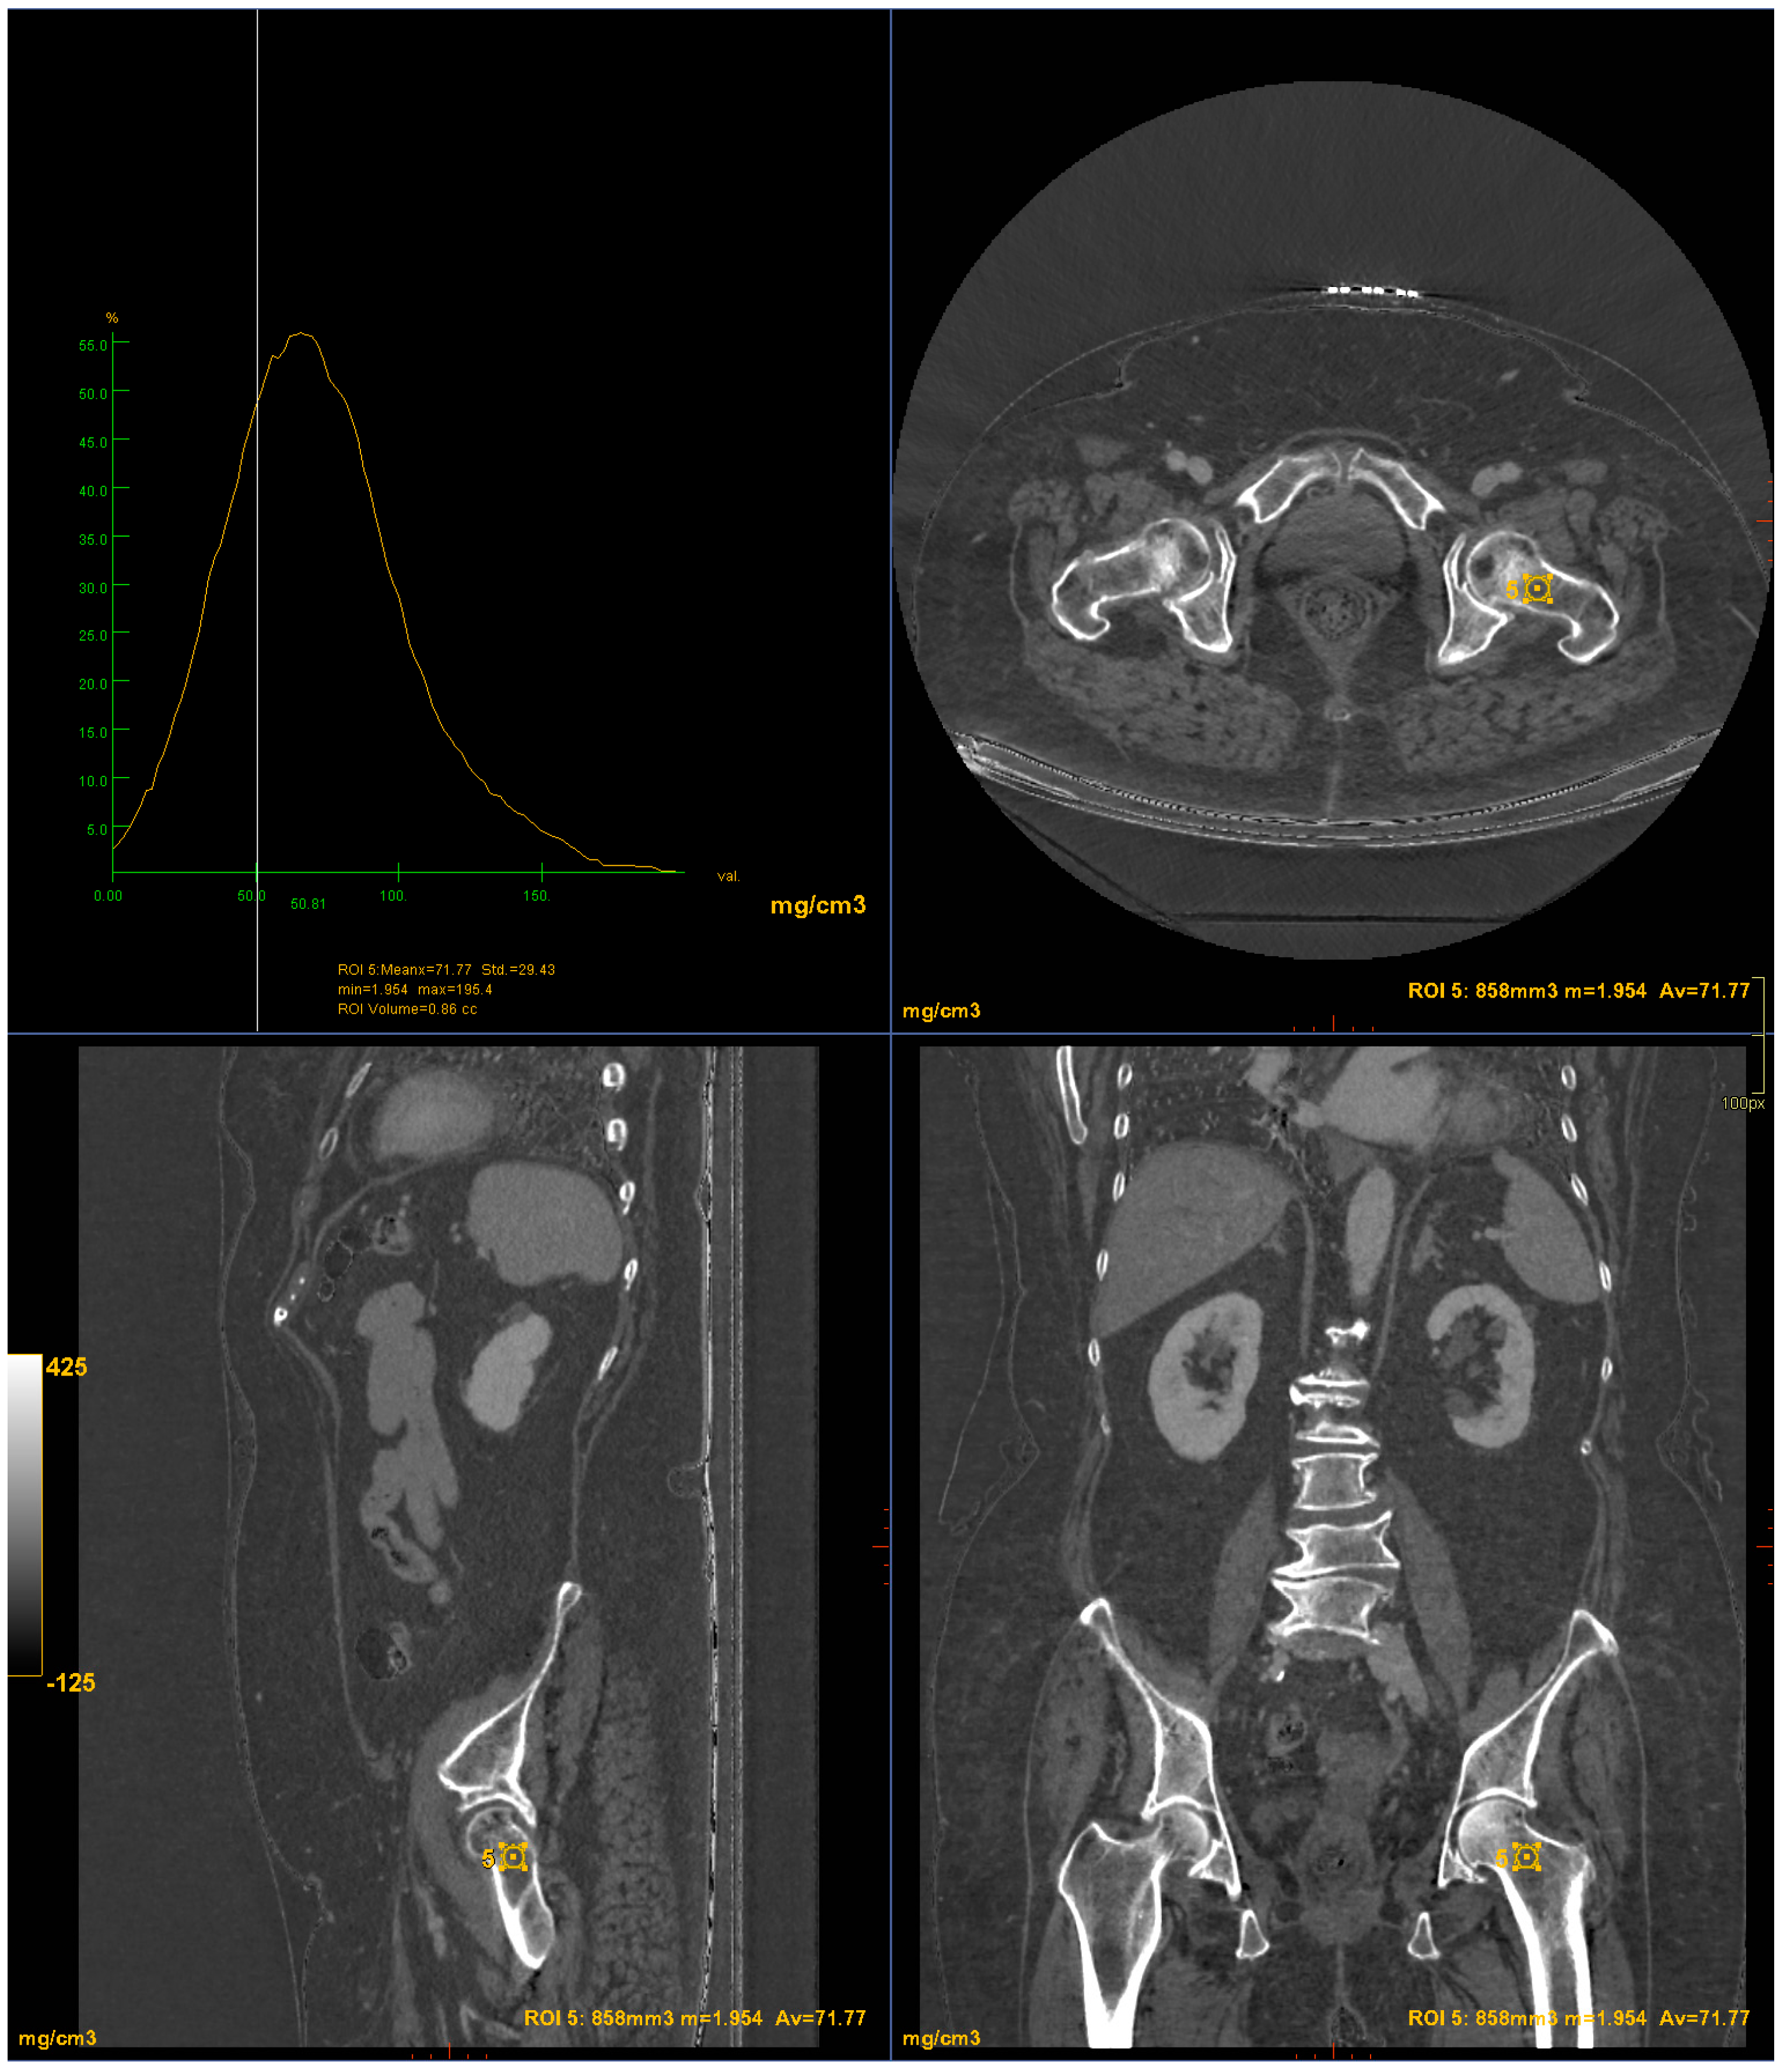

2.2. Imaging

2.3. Postprocessing

3. Results